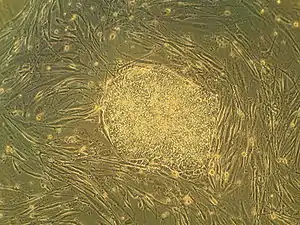

Human embryonic stem cells in cell culture